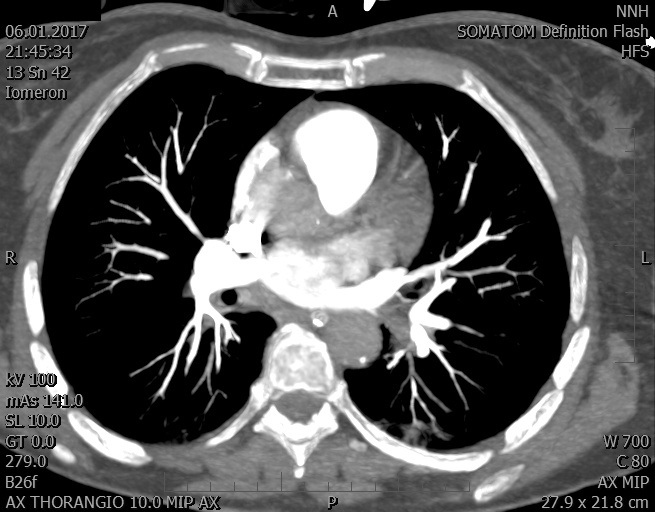

Video 1 - Akutní koronarografie prokázala normální nález na věnčitých tepnách s výjimkou suspekce na lehký spasmus na pravé koronární tepně.Echokardiograficky byla zjištěna těžká dysfunkce dilatované levé komory s nezvětšenou pravou komorou (video 2).

Video 2 - Echokardiograficky byla zjištěna těžká dysfunkce dilatační levé komory s nezvětšenou pravou komorou.Pro nejasnou příčinu zástavy jsme provedli i vyšetření výpočetní tomografií (CT), které vyloučilo plicní embolizaci (série 1 - soubory na konci článku). V den přijetí při přetrvávající oběhové nestabilitě byla nemocná opakovaně defibrilována pro fibrilaci komor se stabilizací rytmu po podání amiodaronu a mesocainu. Dle hemodynamických měření se jednalo o těžký kombinovaný šok. Vstupní laboratorní vyšetření bylo bez větších pozoruhodností. Posléze jsme doplnili anamnézu od příbuzných a zjistili, že pacientka užila do dvou hodin před srdeční zástavou první tabletu amoxicilinu na lehký respirační infekt. Při nevýtěžnosti vstupních vyšetření a nových anamnestických informacích jsme doplnili 14 hodin po kolapsu vyšetření koncentrace tryptázy v séru, která byla extrémně zvýšena (tabulka 2), což nás vedlo k podezření na anafylaxi.